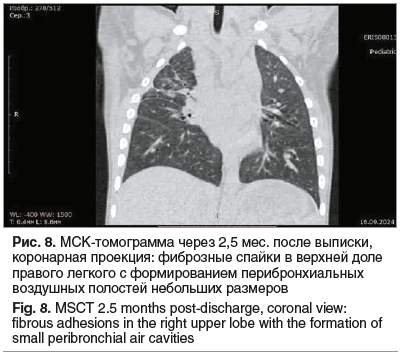

Ребенок осмотрен через 4 мес. после выписки из стационара. Состояние и самочувствие мальчика удовлетворительные. При контрольной МСКТ ОГП от 16.09.2024 (через 2,5 мес. после перенесенного заболевания) в верхней доле правого легкого определяются фиброзные спайки с формированием перибронхиальных воздушных полостей до 2 мм в диаметре (рис. 8). При повторной МСКТ ОГП в октябре 2025 г. сохраняются описанные поствоспалительные изменения без клинических проявлений.

Приведенное клиническое наблюдение следует трактовать как обширный некроз легкого с тяжелейшим поражением органа и бурным развитием патологического процесса на фоне системной воспалительной реакции, неизбежной деструкцией обширной зоны с быстрым и предсказуемым формированием бронхоплевральных свищей, несмотря на адекватную терапию. Слаженная работа команды специалистов с участием торакальных хирургов, пульмонологов, реаниматологов, специалистов лучевой диагностики позволила успешно курировать пациента с крайне тяжелой формой пневмококковой деструкции легких. Однако обширный некроз легкого привел к необратимым изменениям в виде фиброзных спаек с формированием единичных перибронхиальных воздушных полостей в верхней доле правого легкого.